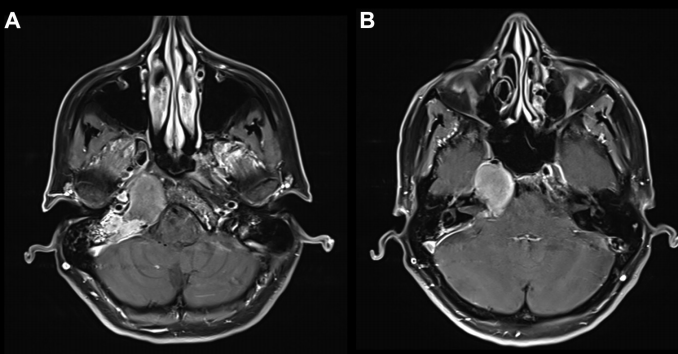

47岁的Emma突然遭遇“耳聋+脸痛”双重打击!起初以为三叉神经痛,谁知一次关键MRI检查竟揪出潜伏在岩尖区的病变——胆固醇肉芽肿。增强 MRI 显示病灶在岩尖、耳蜗和内听道侧面和后部出现均匀强化病灶, T2 低信号和 T1 高信号,病灶导致右侧内听道 ICA 和海绵窦向前移位(图 A 和 B)。

术前MRI